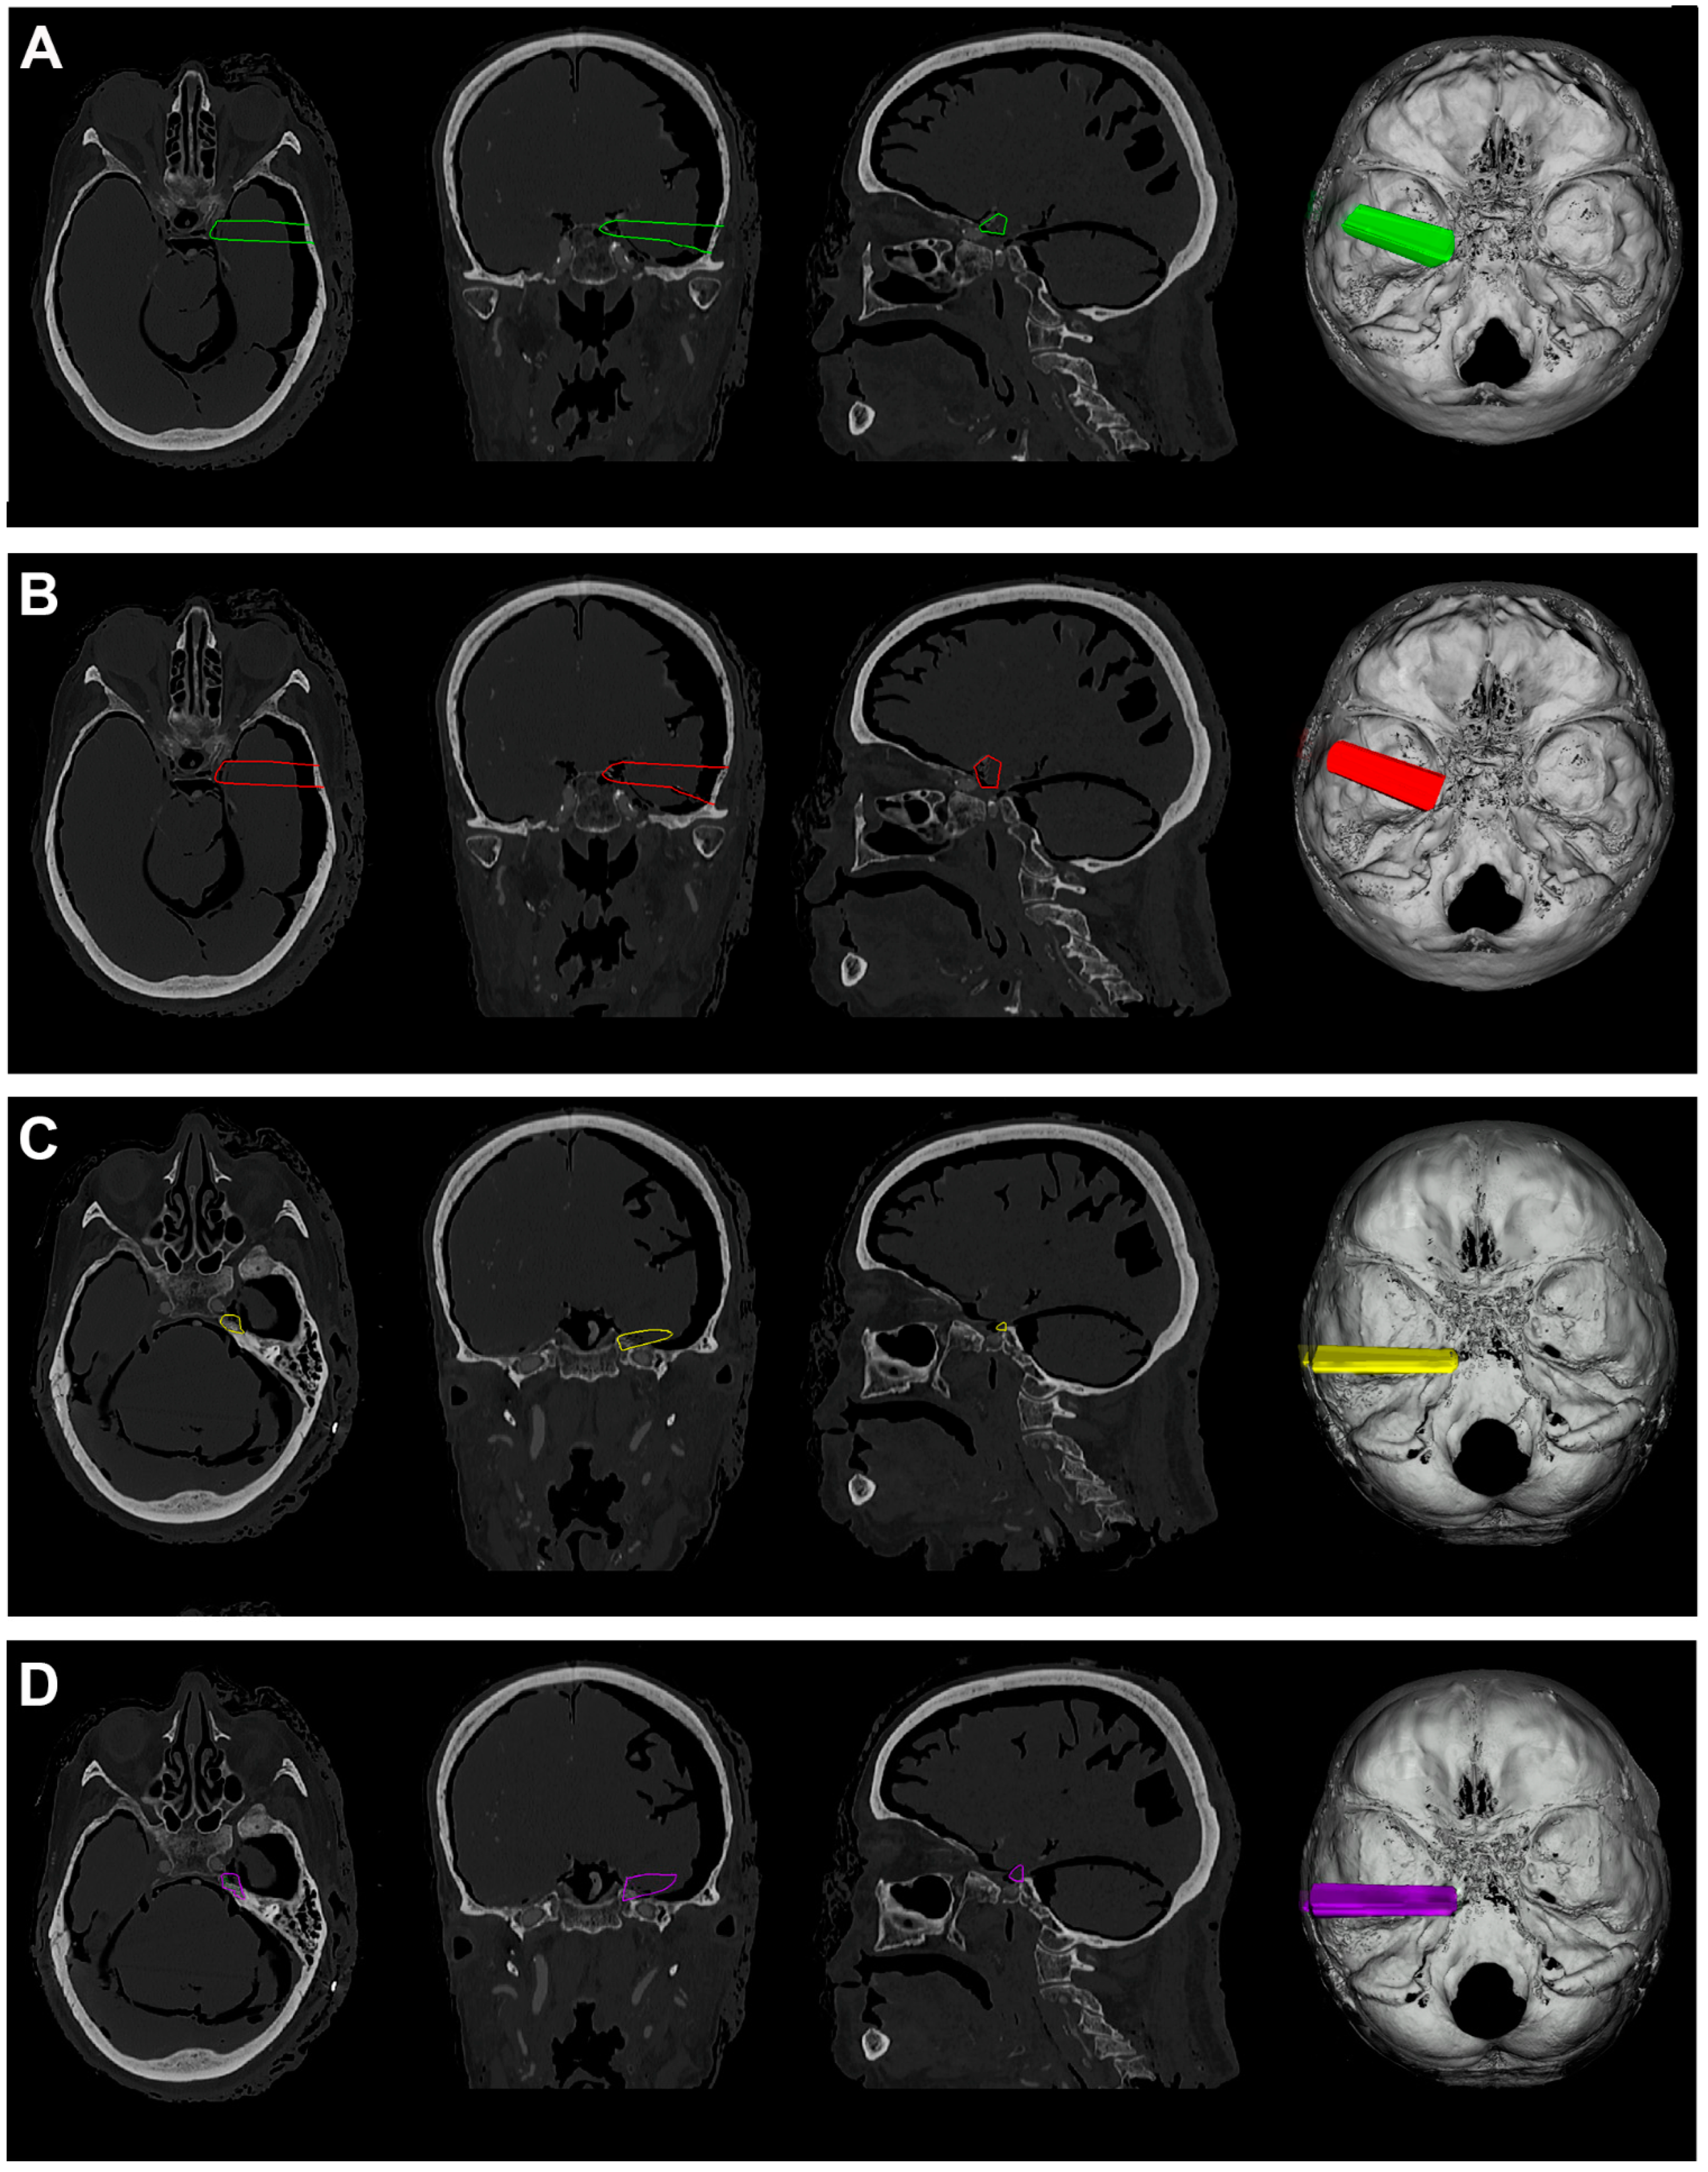

Figure 5.

(A). Exemplificative screenshot from Approach Viewer of the STA with 10 mm of retraction. (B). Exemplificative screenshot from Approach Viewer of the STA with 15 mm of retraction. (C). Exemplificative screenshot from Approach Viewer of the KWA with 10 mm of retraction. (D). Exemplificative screenshot from Approach Viewer of the KWA with 15 mm of retraction.